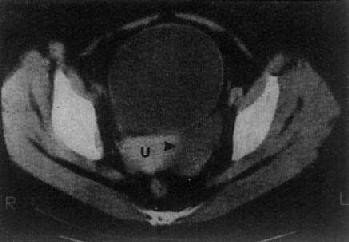

(三)卵巢囊肿或肿瘤 单纯的卵巢囊肿,大多是潴留囊肿,常较小,CT易于显示。表现为囊性低密度影,CT值接近水,边界光滑整齐,大小常为数厘米(图4-5-8)。囊性畸瘤表现为密度不均的低密度肿块,内含多种组织如脂肪、钙化、牙或骨组织。皮样囊肿,其壁常有钙化。卵巢囊腺瘤常较大。浆液性囊腺瘤可为单房性或多房性,壁较薄,少数可为双侧性。粘液性囊腺瘤壁较厚,常为多房性。它们的CT值约为15Hu,增强扫描其壁和囊均不增强。卵巢恶性肿瘤表现为盆腔或下腹部肿块,呈软组织密度,CT值40~50Hu,肿瘤大多同时具有实性和囊性部分,边缘不规则,这些有别于良性囊腺瘤和单纯性囊肿,增强扫描实体部分有增强。卵巢癌可产生腹水,其CT值偏高,可达60Hu,30%的病例可见腹膜或大网膜转移,表现为前腹壁后方扁平形软组织肿块,密度不均,境界不清。有时可见腹膜、腹腔内及肠壁间结节肿块。CT检查了解卵巢癌的范围和转移情况比判断原发癌更为重要。

图4-5-8 卵巢囊肿

子宫(U)左侧有一长圆形低密度区(→),边界清楚,其CT值与膀胱CT值相似